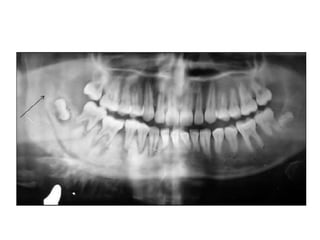

• Most often a well-corticated multilocular

radiolucency.

• “Honey-comb”, “soap-bubble” or “tennis-racket”

appearance.

• May be a well-corticated unilocular lesion

Honeycomb-like small

ameloblastoma at early stage with

evidence of root resorption.

Ameloblastoma

• Soap-like form of

ameloblastoma of the

molar region.

Large multilocular soap bubble appearance.

Typically located in the molar region, angle of the

mandible and ascending ramus

Thin not penetrated cortical plate.

Impacted or neighboring teeth are displaced with

roots often resorped.